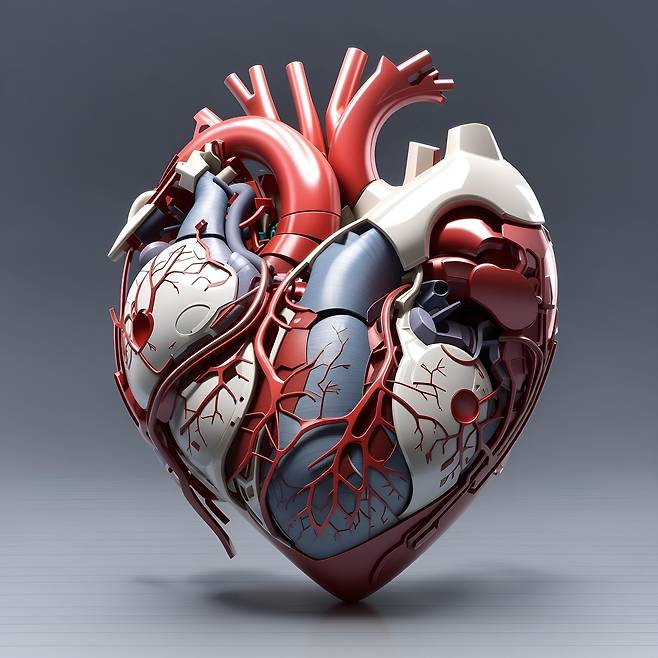

심장은 우리 몸의 펌프 역할을 하는

매우 중요한 기관이지만,